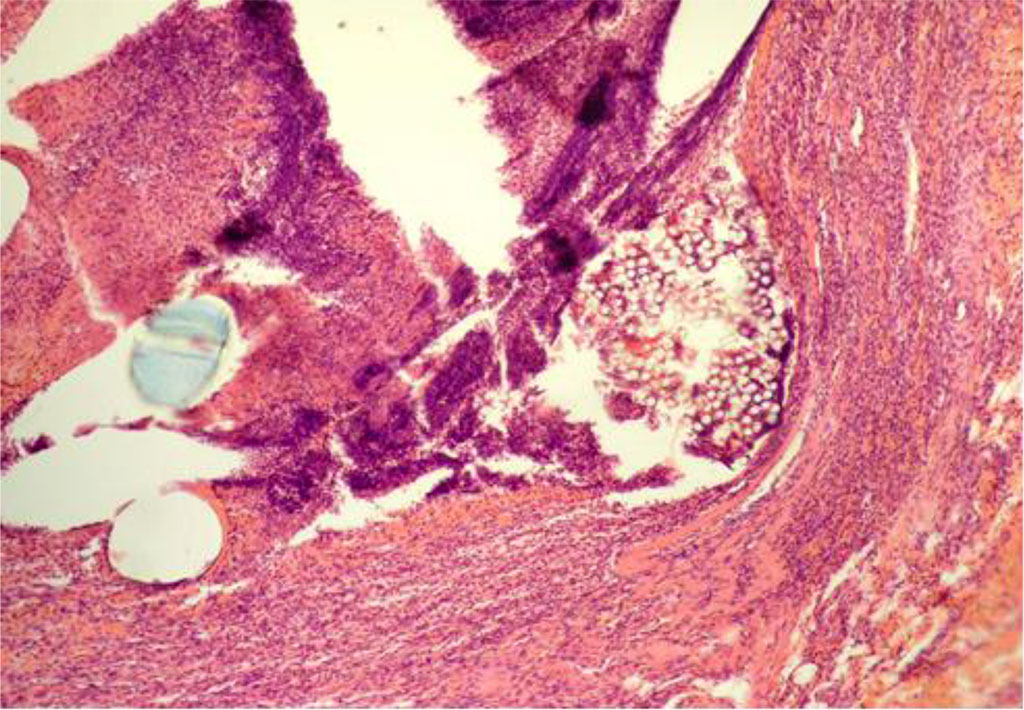

According to the data of the study, by Day 7 of the experiment animals of the CG showed a pronounced penetration of leukocytes along the circumference of the PP particles of MI. At the same time, the ontogenesis of granulation tissue along the peripheral areas was observed, accompanied by sporadic lymphocytes and histiocytes (Figure 1).

Fig. 1. AAW of the CG animal by Day 7 of the experiment. Staining with H&E. ×10

When measuring the thickness of inflammatory changes (IC) in the circumference of the PP-MI fragments, this indicator was 41.607±0.279 μm (Table 1).